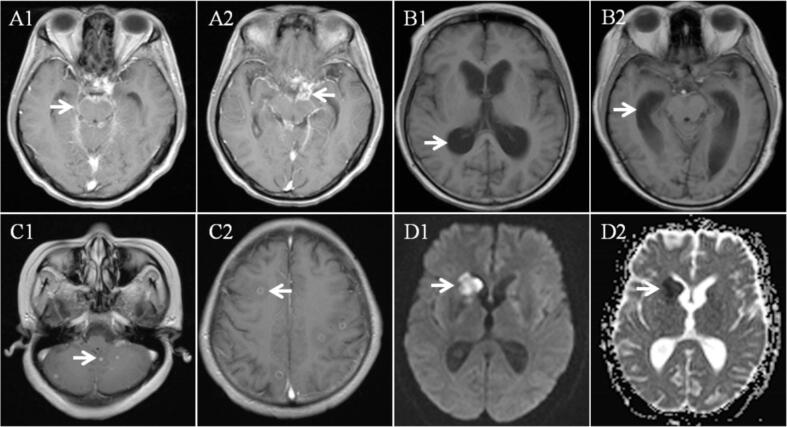

A total of 176 TBM patients were included in the study. Forty-nine patients with stroke were classified as TBMRIS group and 127 patients without stroke were classified as TBM-only group. In TBMRIS group, 41 (83.7 %) patients experienced stroke within 3 months after the onset of meningitis symptoms and 10 (20.4 %) patients presented silent stroke. Stroke occurred in basal ganglia in 57.1 % of patients. About 73.5 % of patients showed multiple stroke lesions and 38.8 % of patients had stroke involving multiple vascular territories. There were significant differences in focal neurological deficit, stage of meningitis, short-term outcome, serum sodium, cerebrospinal fluid (CSF) white cell count, CSF adenosine deaminase (ADA), CSF protein, leptomeningeal enhancement, tuberculoma between TBMRIS group and TBM-only group. Binary logistic regression analysis revealed that focal neurological deficit, CSF white cell count and leptomeningeal enhancement were the independent risk factors for stroke, and tuberculoma was negatively correlated with stroke.

Most of TBMRIS develop within 3 months after the onset of meningitis symptoms and basal ganglia is the most frequent site. Multiple stroke lesions and involvement of multiple vascular territories are commonly observed. Focal neurological deficit, CSF white cell count and leptomeningeal enhancement are the predictors of stroke in patients with TBM.